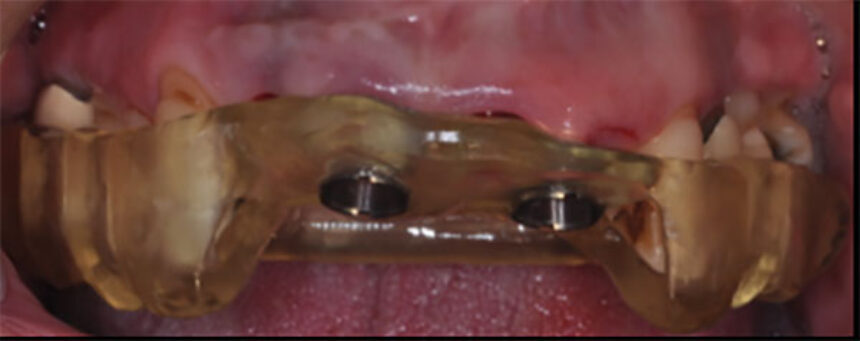

Σε αυτό το online σεμινάριο θα περιγράψουμε τις αρχές, τα πλεονεκτήματα και τα σημεία προσοχής της κατευθυνόμενης τοποθέτησης εμφυτευμάτων. Θα εξετάσουμε αρχικά πως μπορούμε να εκμεταλλευτούμε την ψηφιακή τεχνολογία με λήψη δεδομένων με αποτύπωση μέσω ενδοστοματικού σαρωτή (scanner) και αξονικής τομογραφίας κωνικής δέσμης (CBCT). ‘Επειτα, θα παρακολουθήσουμε πως μπορούμε να συνδυάσουμε τα δεδομένα (matching) ώστε να καταστρώσουμε ένα σχέδιο θεραπείας και σύμφωνα με αυτό να τοποθετήσουμε ψηφιακά τα εμφυτεύματα στην επιθυμητή θέση. Θα δούμε πως σχεδιάζεται ο νάρθηκας για την τοποθέτηση των εμφυτευμάτων, καθώς και η πιθανή προσωρινή εργασία για άμεση φόρτιση.

Στο live χειρουργείο θα γίνουν άμεσα εμφυτεύματα με τη βοήθεια χειρουργικού νάρθηκα για κατευθυνόμενη τοποθέτηση και άμεση προσωρινή αποκατάσταση με ταυτόχρονη λεπτομερή επεξήγηση των σταδίων και των πιθανών προβλημάτων και πως αυτά μπορούν να προληφθούν ή να αντιμετωπιστούν. Επίσης, θα γίνει σάρωση της περιοχής με scanner για την προετοιμασία της τελικής προσθετικής αποκατάστασης.

🔴 της ψηφιακής τοποθέτησης του εμφυτεύματος και του σχεδιασμού του νάρθηκα

🔴 του πρωτόκολλου τρυπανισμού και ελέγχου με το νάρθηκα κατευθυνόμενης τοποθέτησης